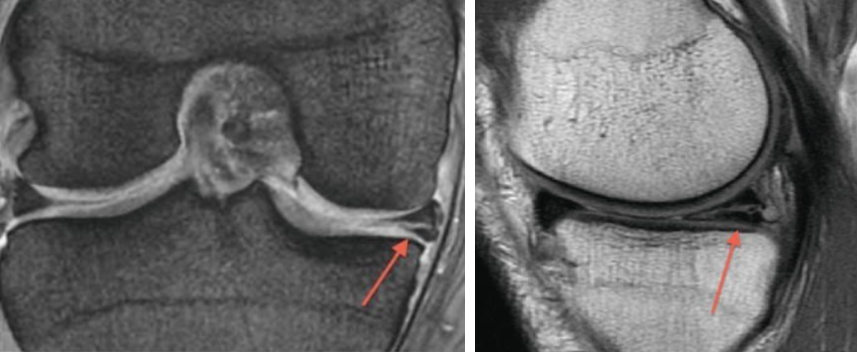

MRI(자기공명영상): 반월상 연골판 파열 진단에 가장 정확한 검사이며, 파열 정도와 위치, 동반 손상 여부를 확인

MRI는 진단 정확도가 약 90~95%에 이릅니다.